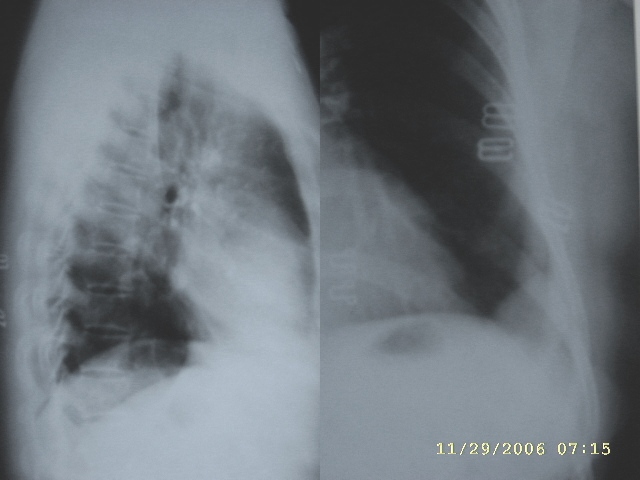

ct图片少又差,还不如就胸片让人来猜,左胸腔包裹性积液.

ct图片少难度太大,我考虑1、左侧包裹性胸腔积液  2、炎性假瘤

ct图片少难度太大,考虑1、左侧包裹性胸腔积液  2、炎性假瘤